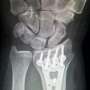

Some lovers try positions that they can’t handle—I’m referring to the bones of the wrist, of course. The phrase is a classic mnemonic used to remember the eight carpal (wrist) bones—scaphoid, lunate, triquetrum, pisiform, trapezium, trapezoid, capitate and hamate—whose initials form the memorable sentence.